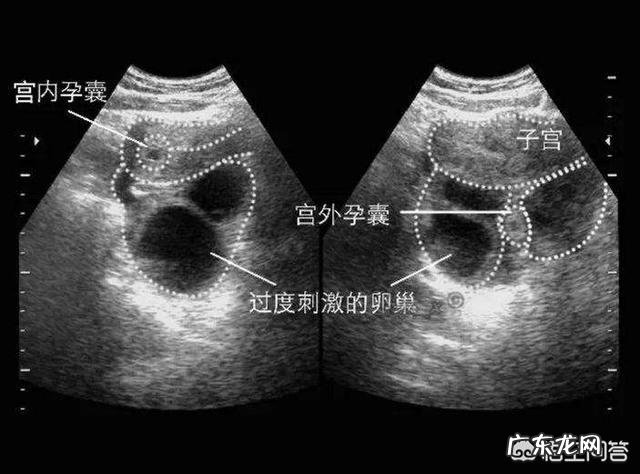

3、b超诊断 , 宫腔内为探及妊娠囊 , 未见胚芽及原始心血管搏动 , 可确诊宫外孕 。